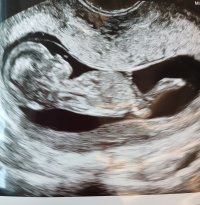

Ei näy nubia tässä kuvassaMiekin tulen kysymään osaako joku tästä meidän kuvasta jotain sanoa. Viikot 13+4. Mulla on sellainen tunne että poika tulisi, mutta tuosta nubista en osaa sanoa mitäänView attachment 138958